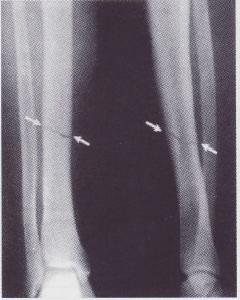

脛骨骨折外固定架組:清創處理後在原傷口基礎上適當延長切口,顯露骨折,直視下骨折復位,使用復位鉗固定。然後在距骨折端4cm以上的脛骨前內側面,分別鑽孔,各擰入兩枚直徑6mm螺紋針,上連線桿固定,檢查骨折復位滿意、固定可靠,縫合傷口。

帶鎖髓內釘:無論開放性或閉合性骨折,首先行跟骨牽引,於傷後7-12天,小腿腫脹消退,患肢無感染徵象時手術。硬膜外麻醉,膝關節屈曲90°,助手牽引復位骨折端並維持,脛骨結節後上0.5cm開孔,依次手動擴髓,插入比擴髓鑽小1mm的備用髓內釘,C型臂透視骨折復位良好,安裝遠近端鎖釘和釘尾螺帽,縫合切口。除1例粉碎骨折閉合復位插釘失敗骨折端切開外,余全部閉合復位插釘成功。術後2-3天疼痛緩解後,不負重下主動練習膝、踝關節活動。